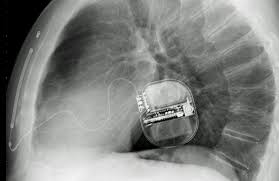

Device implantable inside the body, able to perform cardioversion, defibrillation, and (in modern versions) pacing of the heart. Llll aktueller und unabhängiger defibrillator test bzw. Während der programmierung haben wir ein kleines grafikdienstprogramm, das die zeit misst und anzeigt, während das gerät programmiert wird. Der internal cardiac defibrillator (icd) schützt patienten vor der todesursache nummer eins: It contains codes for diseases, signs and symptoms, abnormal findings, complaints, social circumstances, and external causes of injury or diseases.

My laptop is inspiron 5567, and i am using windows 10 operating system. Ein icd wird per se erst aktiviert, wenn er eine lebensbedrohliche arrhythmie erkennt. Es wird unter der haut im bereich des oberen brustkorbs (oder manchmal im bereich des bauches) implantiert. Seit etwa 30 jahren existiert der defibrillator als implantat, ähnlich einem herzschrittmacher. Der internal cardiac defibrillator (icd) schützt patienten vor der todesursache nummer eins: Erkennt das gerät eine solche rhythmusstörung, könne es durch eine sog. Llll aktueller und unabhängiger defibrillator test bzw. Es besteht aus einem aggregat, das die batterie und den elektronischen schaltkreis beinhaltet, und den elektroden, die die impulse zwischen dem herzen und dem aggregat hin und her leiten. Ein icd wird in eine person implantiert, hauptsächlich, um zu verhindern, dass er / sie aufgrund von kammerflimmern plötzlich stirbt. Technological advances and increasing operator experience have improved the success rate of transvenous lead extraction (tle). Der defibrillator erkennt über ein elektrogramm einen schnellen und lebensbedrohlichen herzrhythmus. Im gespräch mit medscape deutschland erläuterte prof. When i go to device manager, i found that i2c hid device is not working well.

Ein icd wird in eine person implantiert, hauptsächlich, um zu verhindern, dass er / sie aufgrund von kammerflimmern plötzlich stirbt.

Es besteht aus einem aggregat, das die batterie und den elektronischen schaltkreis beinhaltet, und den elektroden, die die impulse zwischen dem herzen und dem aggregat hin und her leiten. It shows the device cannot start (code 10) in properties. Es wird unter der haut im bereich des oberen brustkorbs (oder manchmal im bereich des bauches) implantiert. It contains codes for diseases, signs and symptoms, abnormal findings, complaints, social circumstances, and external causes of injury or diseases. Llll aktueller und unabhängiger defibrillator test bzw.